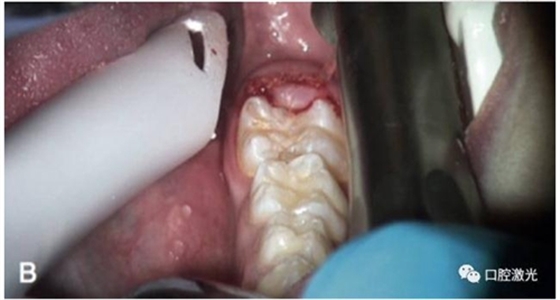

術(shù)中